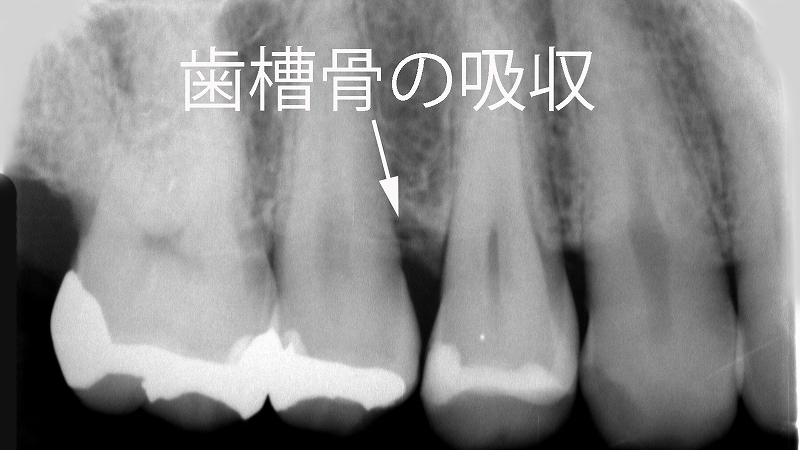

- 5.2. 📸【歯肉増殖部位のレントゲン所見】

- 5.2.1. 🦷【確認された部位】第二小臼歯付近の歯槽骨吸収

📸【歯肉増殖部位のレントゲン所見】

🦷【確認された部位】第二小臼歯付近の歯槽骨吸収

- レントゲン画像では、第二小臼歯部にわずかな歯槽骨の吸収を確認

- 増殖した歯肉の周囲に軽度の骨変化が認められる

📷レントゲン診断と薬剤調整・炎症のコントロールを組み合わせた治療が効果的です。